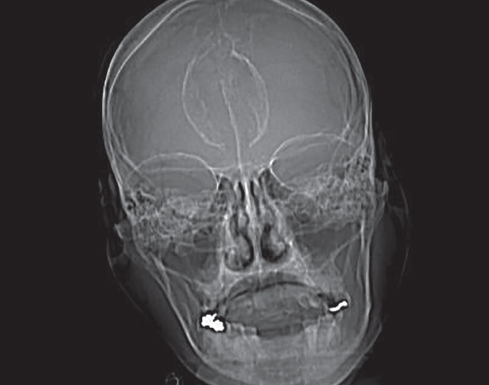

Hanns Frimpong, MS; Ronda D. Edwards, MPH; Syed A.A. Rizvi, PhD, MBA; Sultan S. Ahmed, MD

A 33-year-old Asian American female who came to our practice with her husband complaining of intermittent dizziness and near-syncopal attacks that have been going on for 10 years now.